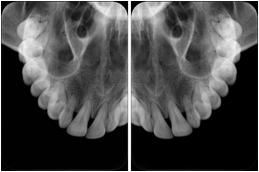

1. A patient in rural Canada visits a general ophthalmologist and is found to have diabetic macular edema. The general ophthalmologist would like to discuss the case with a retina specialist before performing laser surgery. A fluorescein angiogram is done with multiple retinal images taken in a timed series after an intravenous injection. The images along with a Structured Display are shared via a Health Information Exchange with a retina specialist in Calgary, who opens them using his Ophthalmology EMR software and consults via phone with the general ophthalmologist. Both physicians view the images in the same layout so the retina specialist can provide accurate guidance for treating the patient.

2. A patient in rural Iowa visits his primary care physician for management of diabetes. Three non-mydriatic (patient's eyes are not dilated) photographs are taken of the back of each eye, and forwarded electronically along with a Structured Display to an ophthalmologist in Iowa City. The ophthalmologist reads the photos in an agreed upon layout so there is no mistake about what portion of which eye is being viewed. The ophthalmologist is able to tell the primary care physician that his patient does not need to come to Iowa City for face to face ophthalmologic care, but that there is a particular view of the left eye that should be photographed again in 6 months.

Ophthalmic Retinal Study Structured Display

Figure OO-3. Ophthalmic Retinal Study Structured Display